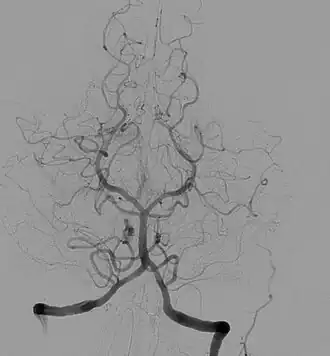

Ангиогра́фия (греч. ἀγγεῖον — сосуд + γράφειν — писать) — класс методов контрастного исследования кровеносных сосудов, используемый в рамках рентгенографических, рентгеноскопических исследований, в компьютерной томографии, магнитно-резонансной томографии, применяемый в гибридной операционной с использованием рентгеноконтрастного вещества[1].

Ангиография показывает функциональное состояние сосудов, окольного кровотока и протяжённость патологического процесса. Исследование позволяет выявить повреждения и пороки развития кровеносных сосудов: аневризмы, сужения сосудов, мальформацию, нарушения проходимости сосудов (атеросклероз, тромбоз), а также повреждения и пороки развития различных органов, опухоли[2]. Например, ангиограмма сосудов головного мозга со специфической картиной помогает диагностировать болезнь моямоя[3].